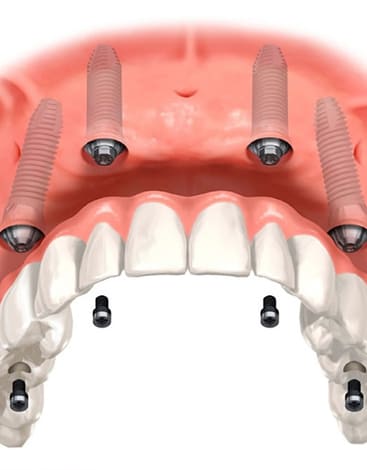

医院全体で1000本以上の実績

安心のインプラント治療

当院では1000本を超えるインプラント治療の実績に基づき、CTによる精密な診断のもと、安全性を優先した治療計画を立案します。 骨造成など難度の高い症例にも対応可能です。 失われた歯の機能と見た目を取り戻すための、良質な方法をご提案します。